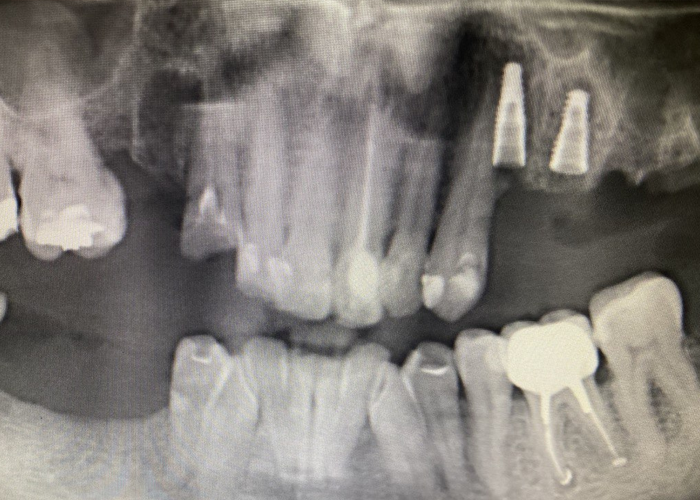

It'sGeorgy Опубликовано 28 мая, 2021 Поделиться Опубликовано 28 мая, 2021 Здравствуйте. 21.05.21: Язычносмещенный разрез, удаление оставленного корня 2.4, удаление 2.6 и 3.8. Имплантаты 2.4, 2.5. Пошел сделал снимок: Не понравился дистальный наклон 2.5, пошел перекручивать. Пока крутил-вертел торк с 25 упал до пальцевого. Принял решение установки коротких формиков, ССТ вестибулярно и ушивания наглухо. Сегодня пациент пришел на осмотр к другому доктору, а там вот такая печалька: Какие ошибки предполагаю сам: 1. Слишком толстый трансп, ушивание которого вызвало перенатяжение 2. Медиальный шов, который держит трансп совсем хиленький и, на самом деле, мало что держит. И главный вопрос: что делать? Оставлять и надеяться, что что-то приживется или полностью убирать? Ссылка на комментарий

It'sGeorgy Опубликовано 29 мая, 2021 Автор Поделиться Опубликовано 29 мая, 2021 (изменено) Всем спасибо за отклик. Через 2 мес, если не забуду, выложу фото результата. 28.05.2021 в 22:17, АнтонТЛТ сказал: Какой смысл в свободном трансплантате был? По плану было увеличить объем вестибулярно и толщину окклюзионно, чтобы в дальнейшем, на этапе времяшек, дополнительно сместить все в сторону этого дефекта, чтобы его закрыть: 11 часов назад, Женька сказал: Не слишком ли высоко трансплантат забран? не критикую, только интересуюсь. Сложно сказать. При заборе трансп с неба я иглой во время анестезии смотрю участок, где достаточная толщина. Вероятно, в момент операции, эта область показалась наиболее перспективной с этой точки зрения. Сейчас, как сказал @Карен Аванесов , я бы вообще с бугра взял. Да и в целом, с десной бы работал на этапе высоких формиков. Изменено 29 мая, 2021 пользователем It'sGeorgy Ссылка на комментарий

It'sGeorgy Опубликовано 12 июня, 2021 Автор Поделиться Опубликовано 12 июня, 2021 Прошу прощения, что долго не получилось ответить. 03.06.2021 в 00:11, АнтонТЛТ сказал: Я правильно понимаю, что установлены короткие фдм, подшит трансплантат, не было мобилизации и рана ушита наглухо? Верно. 03.06.2021 в 00:11, АнтонТЛТ сказал: Если да, то за счёт чего получилось ушить наглухо? Выходит, что за счет излишнего натяжения. Но, во время операции, мне не показалось, что я сильно что-то тягу. 03.06.2021 в 00:11, АнтонТЛТ сказал: Трансплантат получается не вестибулярно, а окклюзионно пришит. Да. В целом, хотел, чтобы было так: Трансп лежит частично над имплантатами, частично - вестибулярно под лоскутом. Лоскут фиксируется небно . 03.06.2021 в 00:11, АнтонТЛТ сказал: Трансплантат фиксирован обычным П-образным швом? Да, двумя. 03.06.2021 в 00:11, АнтонТЛТ сказал: Есть фото со швами? К сожалению, нет. Вот так вот это выглядело вчера. По-моему, десна возвращается в состояние, которое было до операции. Дальше по плану долгожданная чистка + коррекция домашней гигиены и лечение всего того, что надо полечить. Через 1.5 мес буду открывать имплантаты и устанавливать высокие формики и думать, что дальше. Ссылка на комментарий